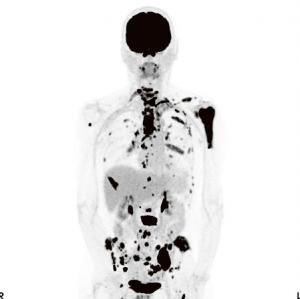

Un radiopharmaceutique est le couplage d’une molécule utilisée dans le métabolisme humain à un isotope faiblement radioactif. Injecté dans le corps, il émet des rayons gamma sous forme de photons émis dans deux directions opposées à 180° précisément. Cette particularité physique permet à la caméra PET de situer le point exact de l’émission. Par exemple: le FDG, un glucose radioactif, se concentre dans les cellules cancéreuses, très avides de sucre. La caméra PET visualise les concentrations de FDG et du coup met en lumière les foyers de cellules cancéreuses.

Sur la caméra PET, un spécialiste peut distinguer les foyers de cellules cancéreuses en analysant les concentrations de FDG (en noir).